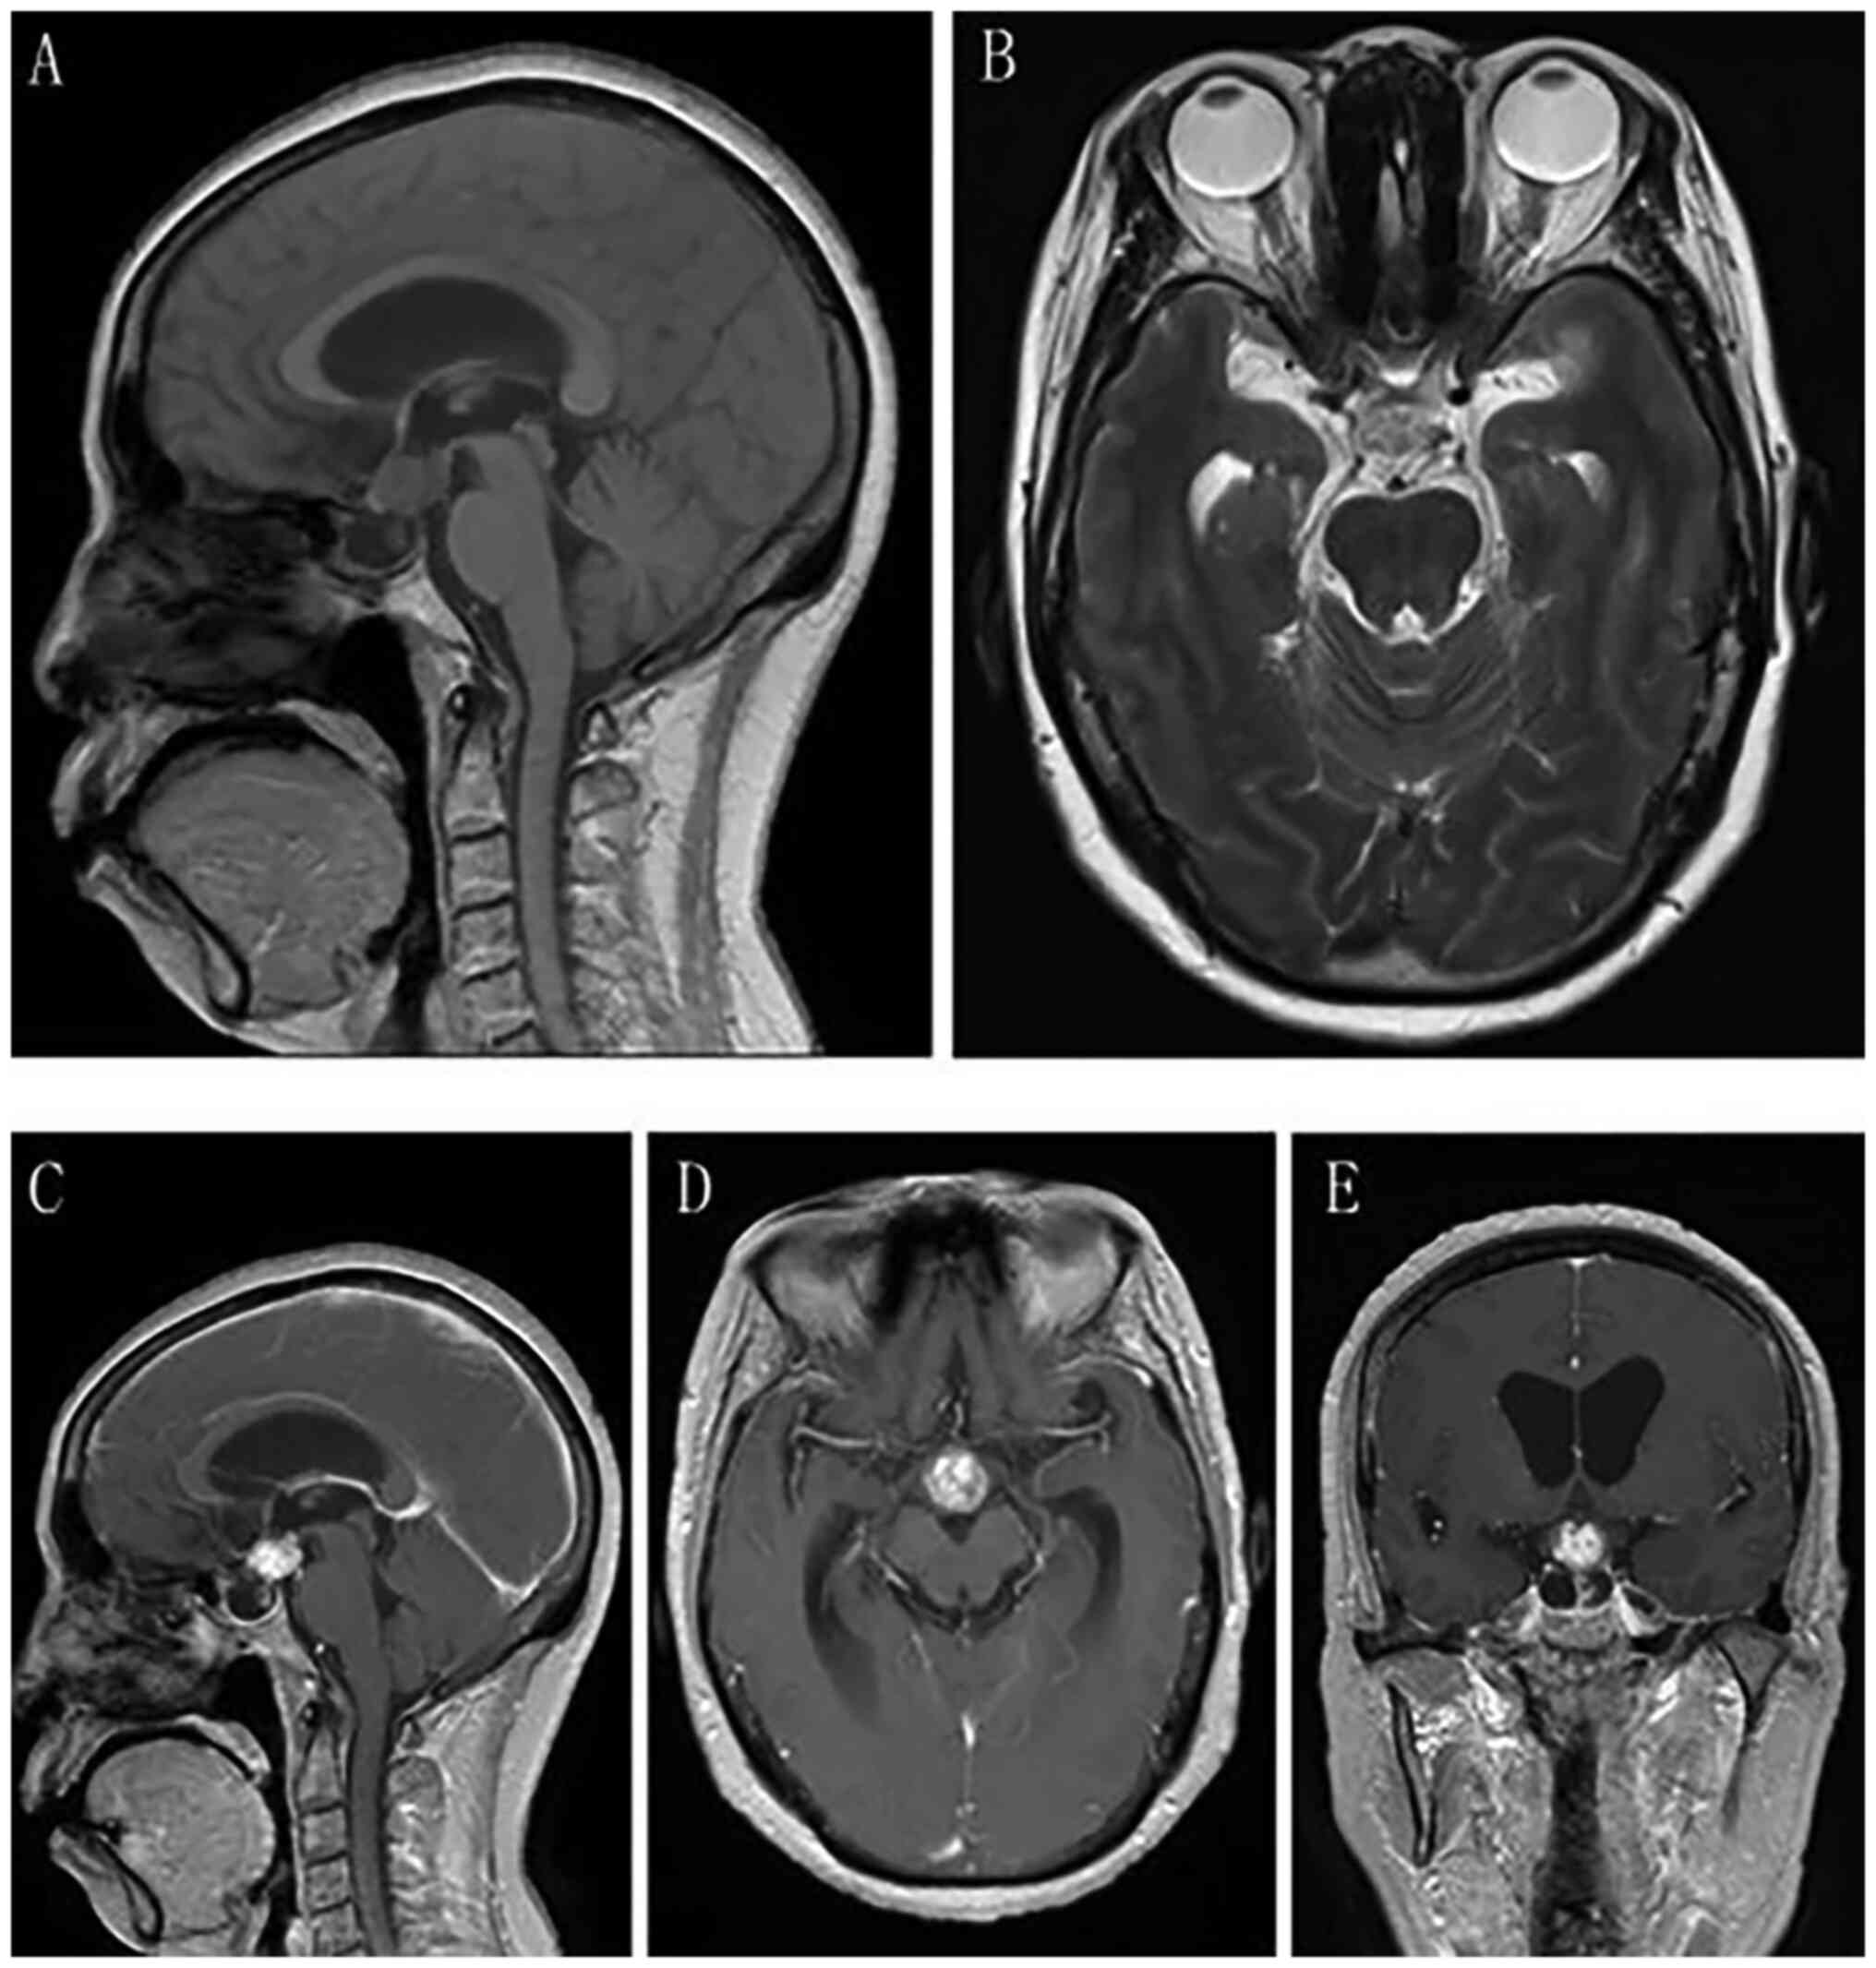

Craniopharyngioma resection and aneurysm clipping performed simultaneously by pure endoscopic endonasal approach: A case report and literature review

Craniopharyngioma is one of the most challenging issues for neurosurgeons as a brain tumor. Among the approaches of neurosurgery, in comparison to craniotomy, the endoscopic endonasal approach (EEA) has risen in popularity over the last two decades; unruptured intracranial aneurysms are relatively commonly found in the general population. The EEA as a new paradigm in the treatment of aneurysm has been reported to successfully clip dozens of cases of intracranial aneurysm. However, when reviewing the domestic and foreign literature, it appeared that cases of craniopharyngioma complicated with intracranial aneurysm purely treated by EEA have not been reported so far. In the present study, the published literature regarding endoscopic endonasal surgery for craniopharyngioma and intracranial aneurysms was reviewed, accompanied with a case of craniopharyngioma complicated with intracranial aneurysm, both of which were simultaneously treated by EEA.